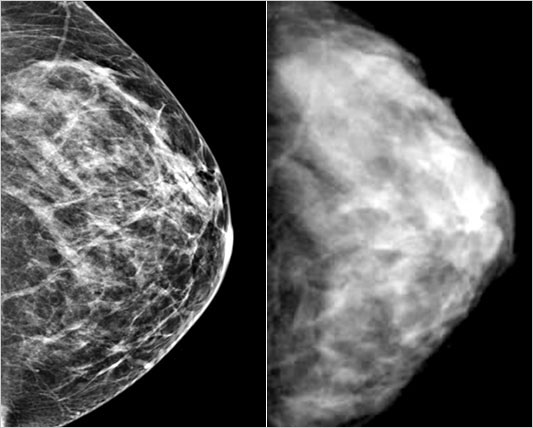

On the left, a normal digital mammogram; a normal mammogram from traditional X-ray film is on the right. (Magee-Women’s Hospital of UPMC)

– Mammograms involve having breasts x-rayed after being squeezed between two plates. by ‘plates’, I’m referring to hospital-grade not dinner (that’s a whole other post that you won’t find on this blog.. or will you… hmm). it’s not pleasant but there are worse things one could do. the mammographer will take pictures of breasts from different angles since obtaining a clear view of the mass isn’t always easy. oftentimes, this is only the first step in your boob ‘photo shoot’.